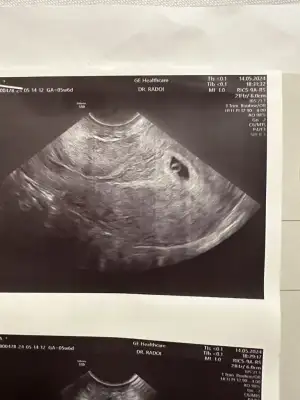

Kızlar selam bugün kese icin geldim tam 5 haftalığız şu an ama karından gözükmedi. Dr beta istedi duruma göre vajinal bakacağım dedii sonuc 3334 çıktı ama doktor acil doğuma gittiği icin bekliyorum bu dğerle karından gözükmemesi normal mi

3bin küsürlerde karından görünmüyormuş benim beta 2151 görünmedi 3 gün sonra gittim beta 6156 çıktı 5+2'dik karından gördük keseyi 9mm dedi. Bende çok tedirgin olmuştum ama sakın kötüyü düşünme birkaç gün sonra tekrar git betanda yükselmiş olur keseyide görmüş olursun Allahın izniyle. 🤲🏻